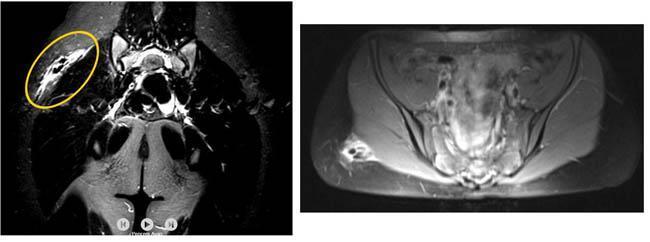

İstanbul'da şoke eden olay! Genç kızın kalçasından çıktı, doktorlar inanamadı

14 yaşındaki ortaokul öğrencisi H.A. 2017 yılının Şubat ayında karda kayıp düştü. Sert bir şekilde kalçasının üstüne düşen genç kız kalçasında bir ağrı hissetmeye başladı. Eve gittiğinde bir kalem ucu gören genç kız ağrısının nedenini buna bağladı ancak geçmeyince doktora gitti.